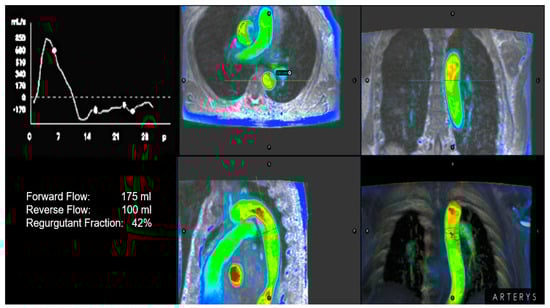

2.4. Cardiac Magnetic Resonance

| CMR | |||

| Regurgitant Fraction (%) | <20 | 20–33 | >33 |

| Regurgitant Volume (mL) | <30 | 30–45 | >45 |

| Reversal diastolic flow in proximal Dao | - | - | Holodiastolic + |